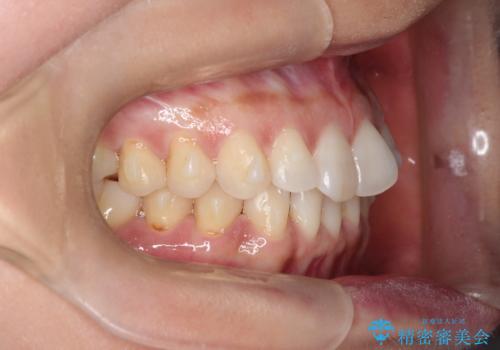

前歯のがたつきと隙間の矯正 インビザラインにて

- 上顎の前歯のがたつきと、下の前歯の隙間を主訴に来院されました。

下の前歯が先天的に欠損していました。

上顎の歯と歯の間をわずかに削りスペースを作り、ガタガタの改善し、下顎の前歯は隙間を閉じる計画としました。

非常に協力的な患者様でしたので、早期に治療が終了することができました。